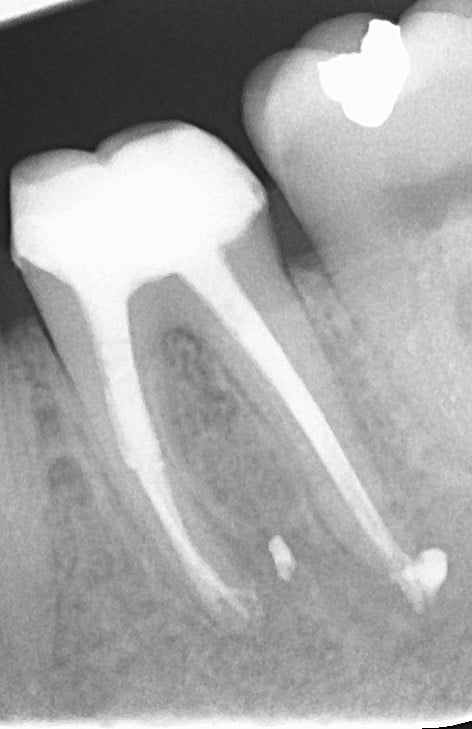

Rentgenový snímek zubu před a po ošetření, kde je vidět, jak pečlivé vyčištění a vyplnění kořenových kanálků obnovuje zdraví zubu a zabraňuje dalším komplikacím.